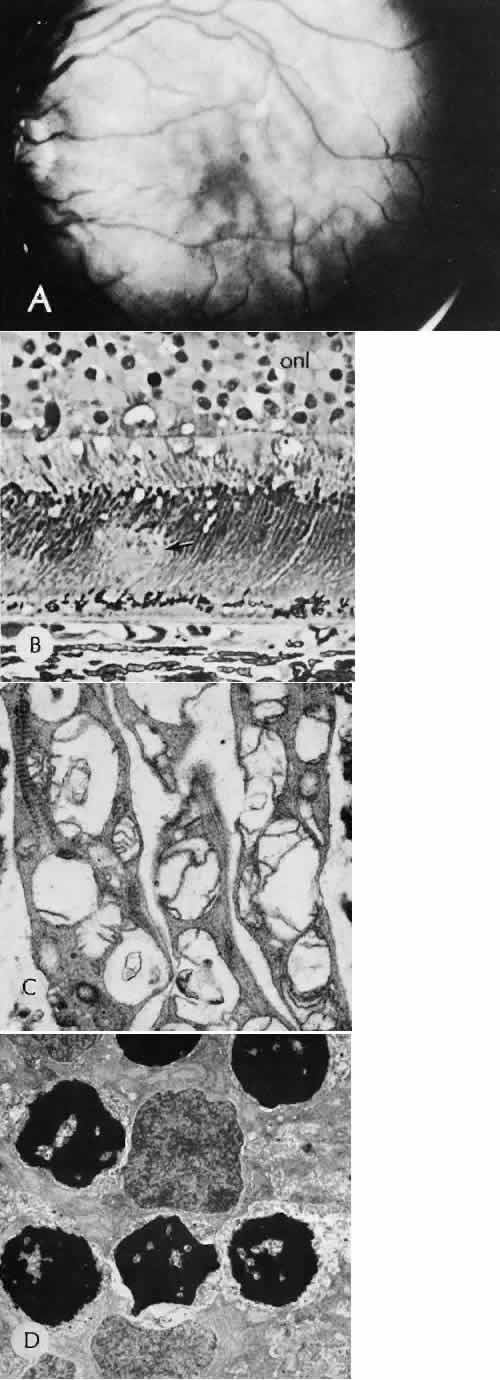

| Successful wound healing in the eye is a precise, ordered series of events